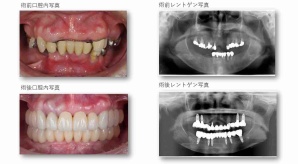

¥¤¥ó¥¹¥¿¥°¥é¥à¤ËºÜ¤»¤Æ¤¤¤ëÅö±¡¤Î¾ÉÎã¤Ç¤¹

ðÌî»õ²Ê¾ÉÎ㢠ÀèÅ··ç»¶ºÀµ¥¤¥ó¥×¥é¥ó¥È

ðÌî»õ²Ê¾ÉÎã¡¶ºÀµ¥¤¥ó¥×¥é¥ó¥È¥»¥é¥ß¥Ã¥¯